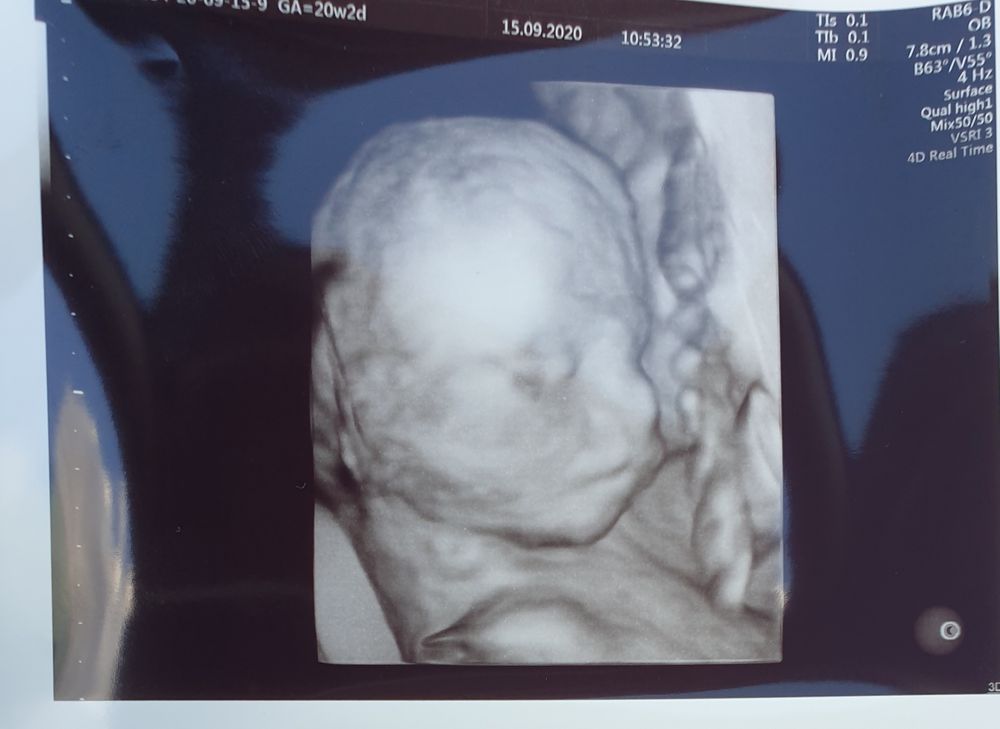

Trinnity, нет, все делала в 3д в платной клинике. Вот, кстати, какие они в 20 и 30 недель 😄 Изображение Изображение

Весь осмотр был в 2д, но несколько раз включали 3д для фото. Фото распечатали (их много). В формате 3д видео, в своем случае, ничего толкового не увидела. Плацента сливалась с лицом и все ооочень приблизительно. 2д видео для меня было понятнее. А на 3д фото один в один изображение младенца, врач сделала чётче некуда (на сроке 25н).